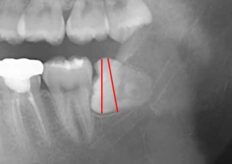

親知らずが水平埋伏(真横に向いていて埋まっている)の状態でした歯茎がはの2/3ほどかぶさって

ブラッシングができない状態でした。

レントゲン像では根尖が下歯槽神経に接触している状態ですが、抜歯をおこなっても神経の損傷

にはならないと判断をしましたので麻酔を行い分割抜歯を行いました。